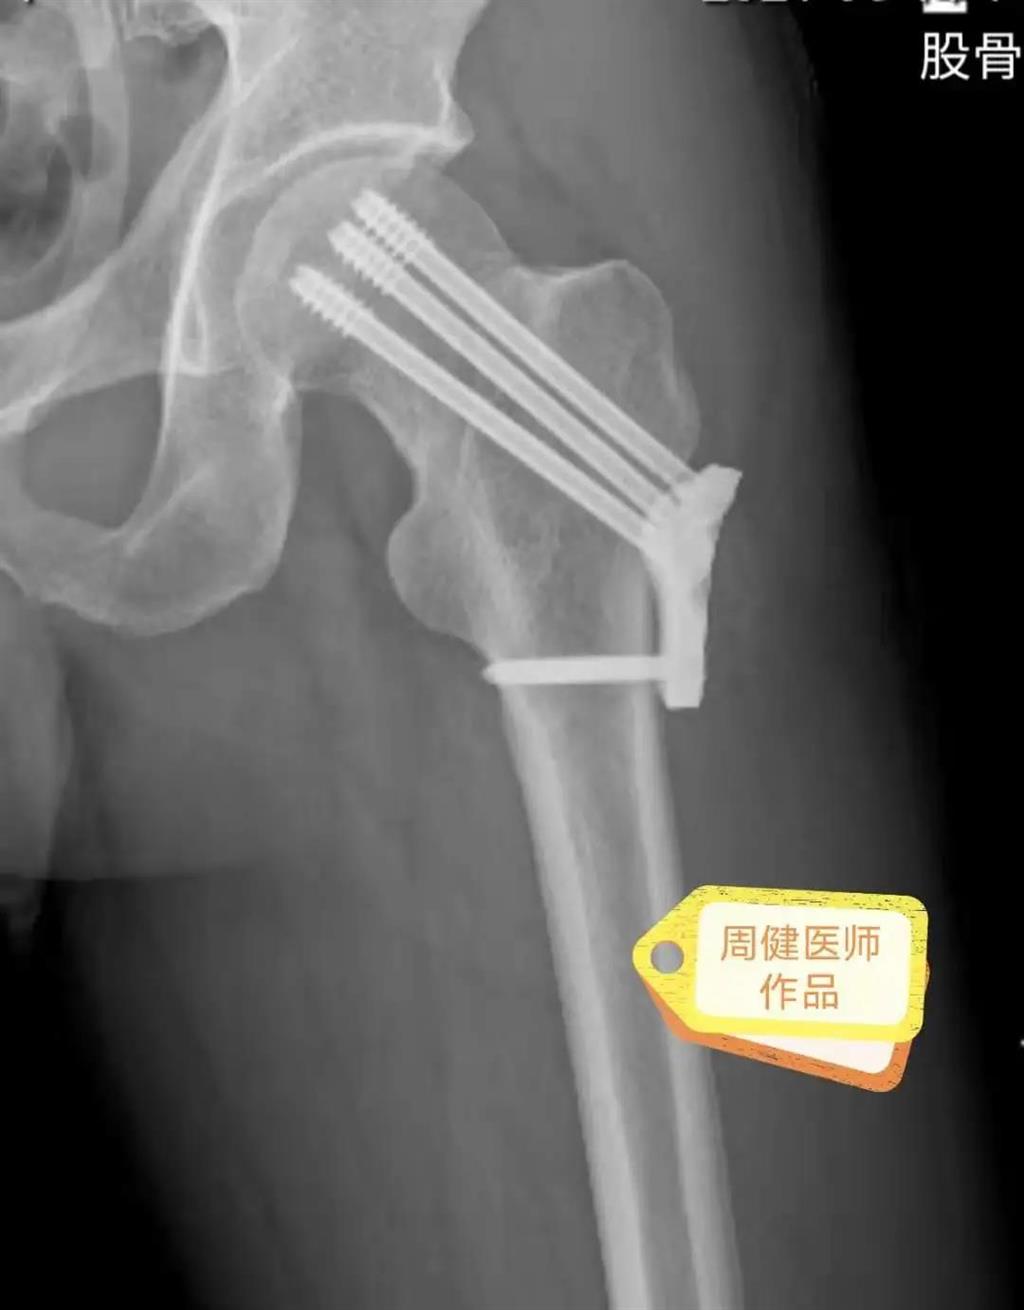

6月30日的“關節置換術”,患者是一位上了年紀的老人,苦于病痛折磨多年的他四處“求醫問藥”,最后在多位專家醫師及病友地力薦下選擇了和平國際醫院,在醫師團隊“偷天換日”般的手術后,老人成功告別了苦纏多年的病痛。

周健說,這場“關節置換術”對于他們團隊而言其實算是比較普通的手術,因為做過很多同類的手術,成功案例繁多,因此在手術操作上有較多地實操經驗。“不過話雖如此,作為醫生我們對于每一場手術都會全力以赴,這是為醫者的職責也是義務。”